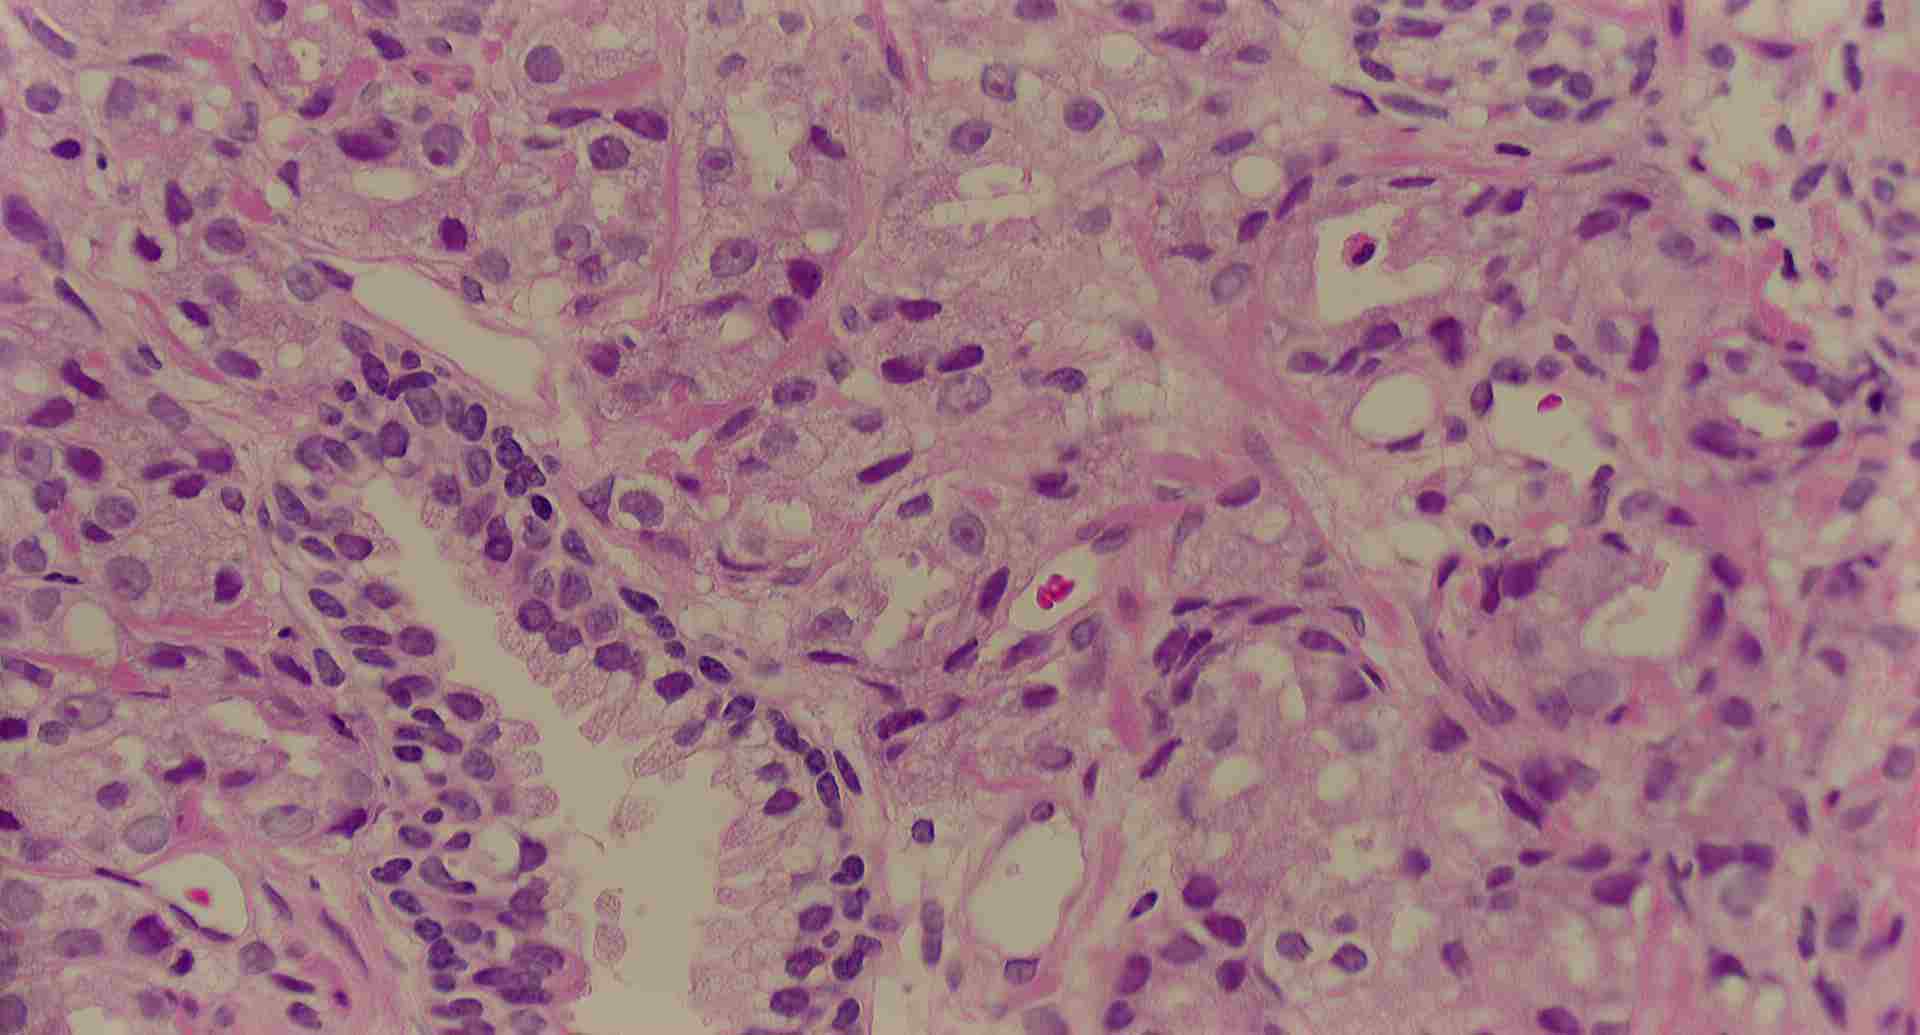

標本の説明

標本11